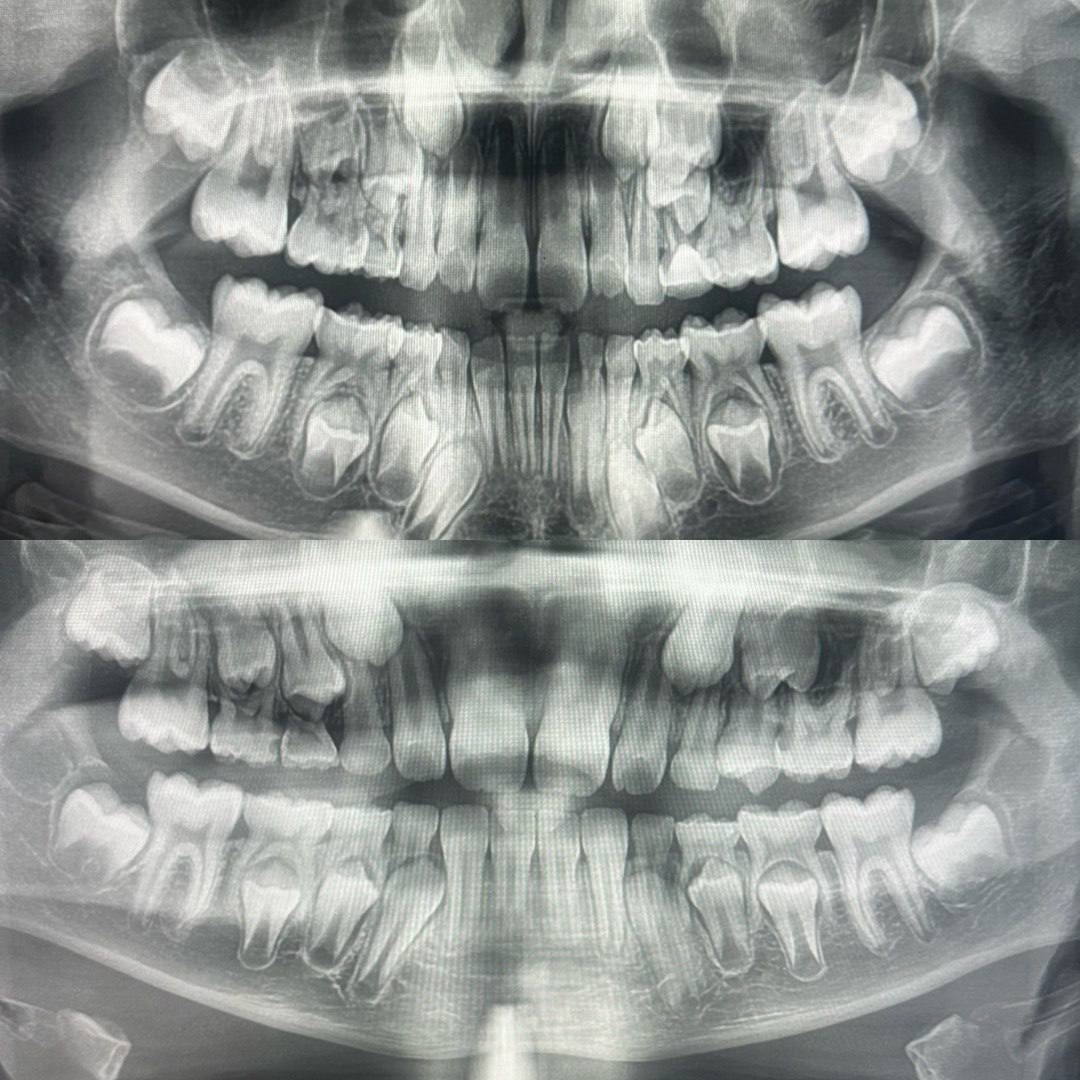

🔡🔡🔡🔡 (ортопантомограмма) одного и того же пациента ⬆️ с разницей в два года Вы можете наблюдать, как меняются зачатки, уже прорезавшиеся зубы и в целом, что картина в полости рта меняется по мере взросления пациента. На что мы всегда обращаем внимание при первом таком исследовании: мы обязательно пересчитываем 🧮 все зачатки постоянных зубов, это чрезвычайно важно! 😔 Ситуация с отсутствием зачатка одного или нескольких зубов становится всё более распространенной, именно поэтому мы имеем некоторую настороженность в этом моменте. Сначала зачаток предстает перед нами в виде коронки зуба в оболочке, далее мы можем наблюдать, как он приобретает все более похожие на зуб очертания, постепенно вытесняя и подталкивая молочный зуб, корни которого начинают рассасываться, зуб становится подвижным и идет 🧳 «на выход» #стоматолог #Москва

Вы можете наблюдать, как меняются зачатки, уже прорезавшиеся зубы и в целом, что картина в полости рта меняется по мере взросления пациента.

Сначала зачаток предстает перед нами в виде коронки зуба в оболочке, далее мы можем наблюдать, как он приобретает все более похожие на зуб очертания, постепенно вытесняя и подталкивая молочный зуб, корни которого начинают рассасываться, зуб становится подвижным и идет 🧳 «на выход»